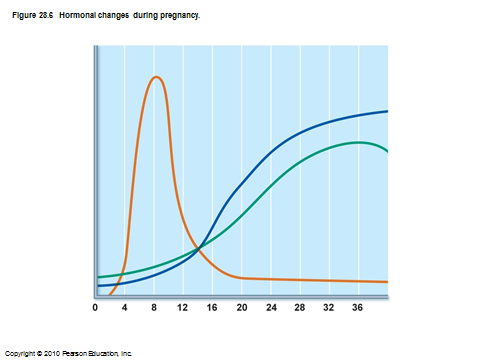

names of hormones during pregnancy

first long graph is beta hCG

second one is estrogen

third is progesterone